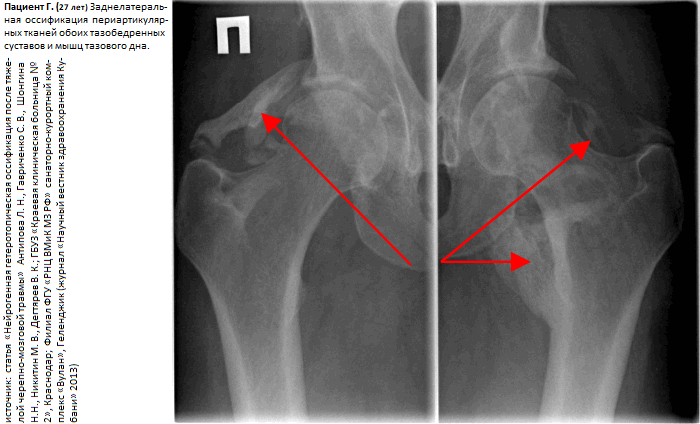

Нейрогенная гетеротопическая оссификация

Гетеротопическая оссификация (ГО) - это появление костных пластин в мягких тканях, в норме не имеющих оссификатов. Появление костной ткани в нетипичных местах чаще всего описывается при травматическом повреждении тканей, в т.ч. и после ортопедических операций. Возникновение оссификатов в неповрежденных тканях у пациентов с поражением центральной нервной системы (ЦНС) классифицируется как нейрогенная гетеротопическая оссификация (НГО).

Наиболее часто НГО встречается при спинальной травме, тяжелой черепно-мозговой травме, инсульте, детском церебральном параличе. Согласно современным литературным данным, встречаемость НГО составляет около 11 - 20 % после тяжелой черепно-мозговой травмы и 20 - 53 % после травмы спинного мозга. В то же время при нетравматической миелопатии НГО диагностируется в 6 - 15 % случаев. НГО после тяжелой черепно-мозговой травмы наиболее часто развивается в периартикулярных тканях тазобедренного сустава, несколько реже - локтевого сустава, еще реже в тканях плеча и области колена.

Клинический симптомокомплекс НГО включает: [ 1 ] ограничение подвижности сустава, [ 2 ] отечность тканей, [ 3 ] повышение температуры, [ 4 ] болезненность мышц и скомпрометированного сустава. Эктопическая кость формируется обычно в области крупных суставов снаружи от суставной капсулы. Оссификаты локализуются в соединительной ткани между пластами мышц, но не в самих мышцах. Позже развивается анкилоз сустава. Иногда разрастающаяся костная ткань компримирует близлежащие нервы. Для заболевания характерна некоторая стадийность течения в виде нарастания, как правило, на протяжении первых 2-х месяцев после травмы, клинических проявлений и постепенное их стихание. Манифестировавшая симптоматика приводит к ограничению движений в суставе, снижению мобильности пациента и ухудшению качества жизни. В то же время к ограничению движений НГО приводит лишь в 10 - 20% диагностированных случаев.

статья «Нейрогенная гетеротопическая оссификация после тяжелой черепно-мозговой травмы» Антипова Л.Н., Гавриченко С.В., Шонгина Н.Н., Никитин М.В., Дегтярев В.К.; ГБУЗ «Краевая клиническая больница № 2», Краснодар; Филиал ФГУ «РНЦ ВМиК МЗ РФ» санаторно-курортный комплекс «Вулан», Геленджик (журнал «Научный вестник здравоохранения Кубани» 2013) [читать];